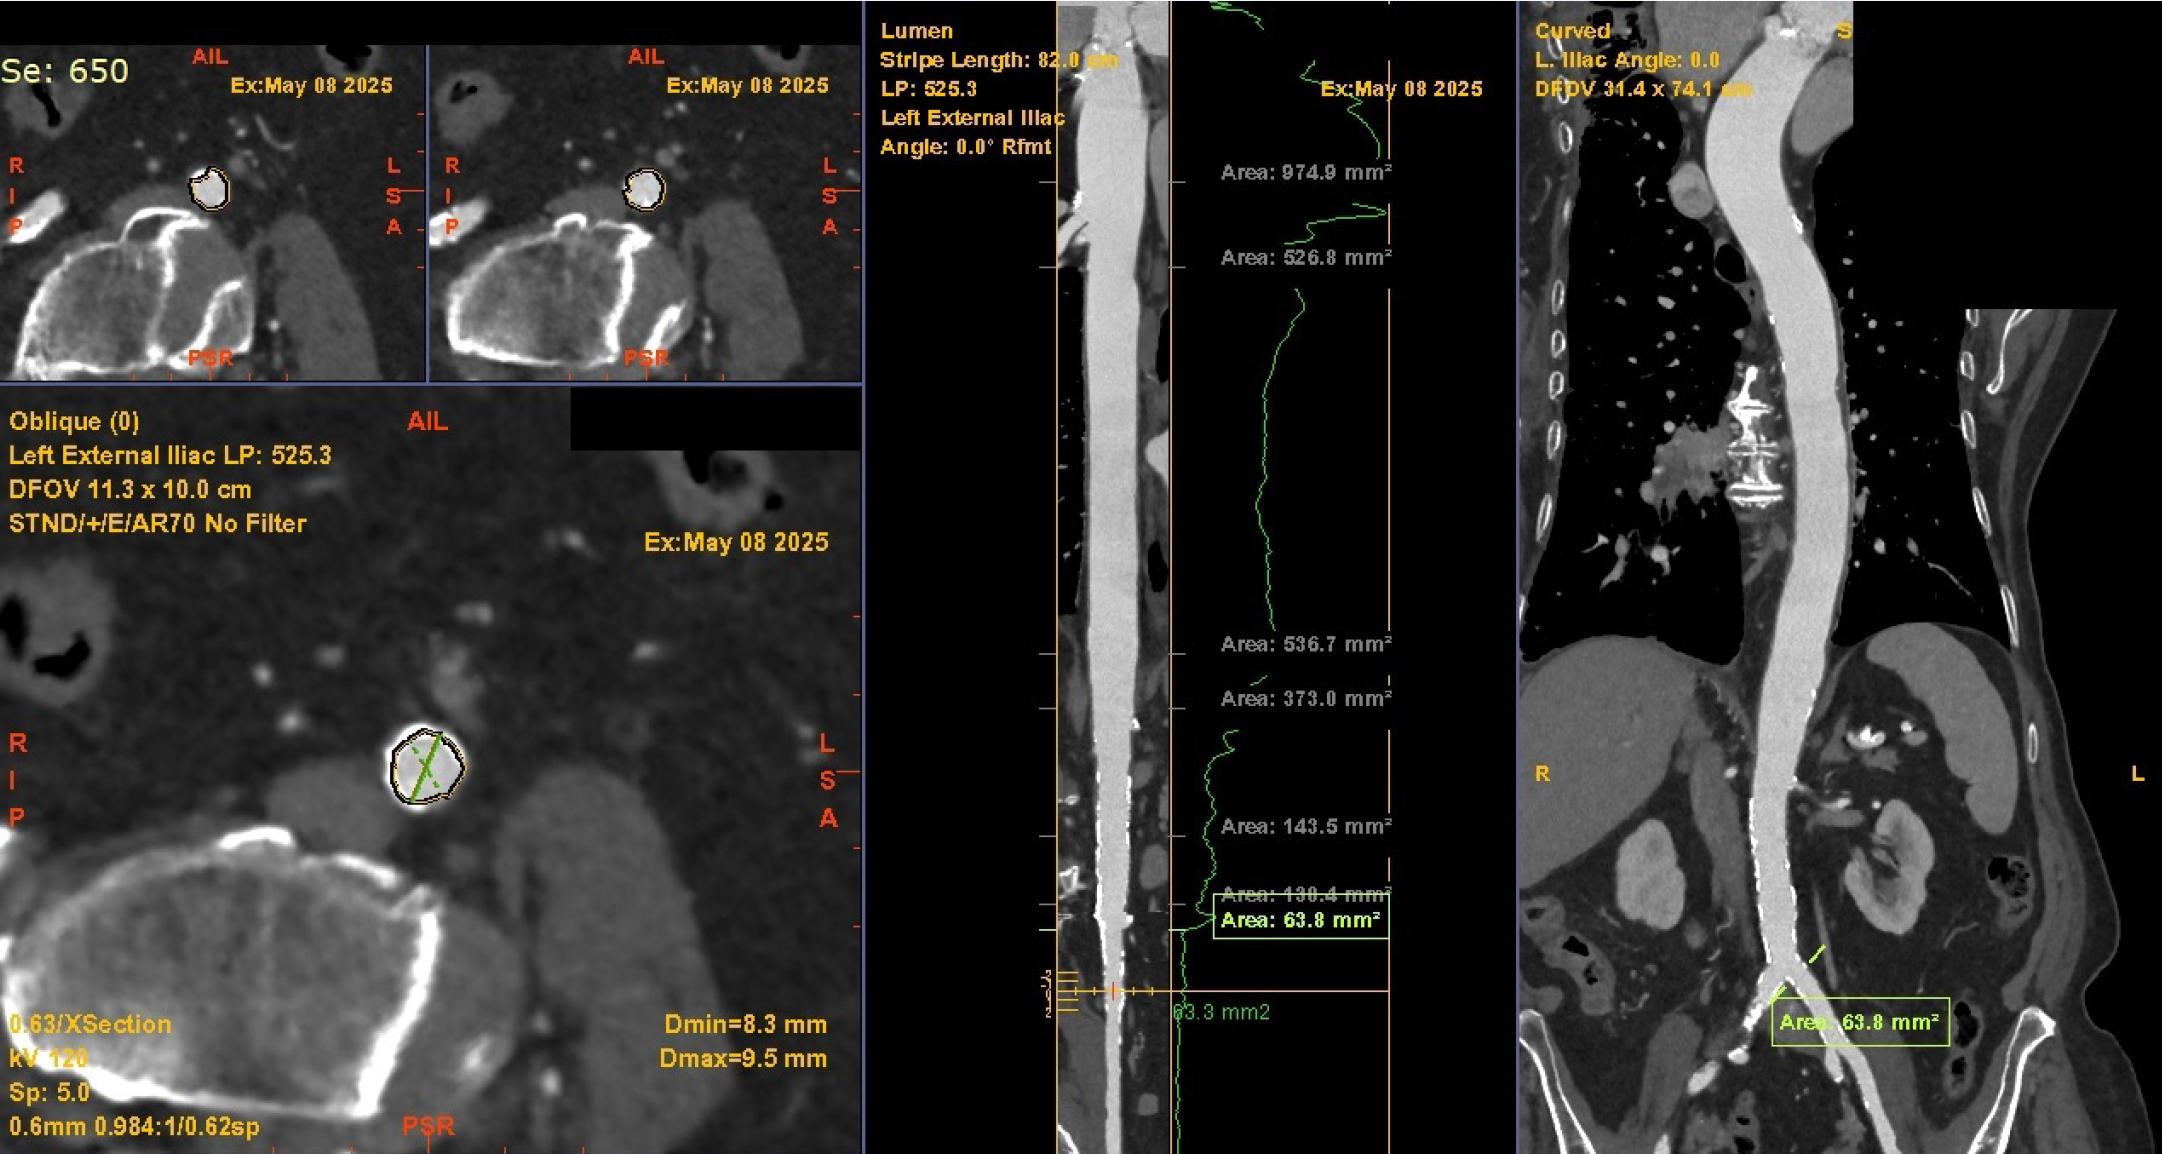

Vascular access assessment for transcatheter aortic valve implantation (TAVI) using computed tomography (CT) angiography. Multiplanar reformatted CT images demonstrating the assessment of iliofemoral access in a patient undergoing TAVI—axial and oblique views (left) and centerline image processing (middle and right) of the left external iliac artery allow assessment of dimensions, calcifications, and angulation critical for evaluating the feasibility and safety of transfemoral access.